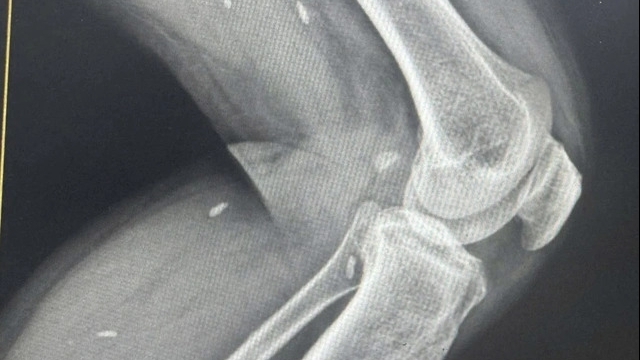

Tiếp đó, bác sĩ chỉ định chụp X-quang cắt lớp. Tuy nhiên kết quả hình ảnh cho thấy, bà không còn thận trái.

Ngày 25/7, bà Nga cùng gia đình tiếp tục quay lại BV Việt Đức để thăm khám lại, bác sĩ vẫn khẳng định không thấy thấy thận trái.